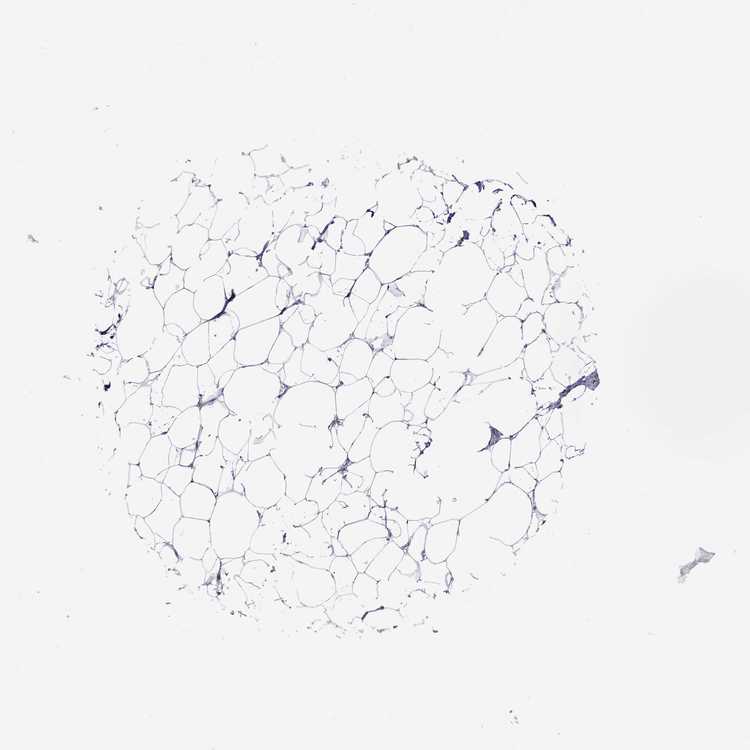

BREAST - Antibody stainingi

Antibody staining in the annotated cell types in the current human tissue is reported as not detected, low, medium, or high, based on conventional immunohistochemistry profiling in selected tissues. This score is based on the combination of the staining intensity and fraction of stained cells.

Each image is clickable and will lead to virtual microscopy that enables deeper exploration of all samples and also displays staining intensity scores, fraction scores and subcellular localization as well as patient and tissue information for each sample.

Antibody HPA065600Antibody CAB055172Antibody CAB080360

Adipocytes Not detectedNot detectedNot detected

Glandular cells Not detectedMediumNot detected

Myoepithelial cells Not detectedNot detectedNot detected